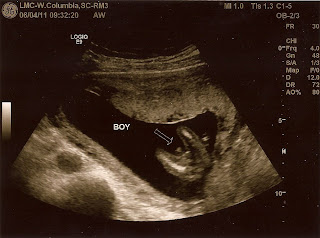

Last weekend I was at the sixteen week mark and I was able to get my first ultrasound pictures since the very first round at eight weeks. Most doctors want to do your ultrasound between 20-24 weeks, but I know people. I have this amazing friend Kristen who is studying to be a tech so we took full advantage and had some fun!

At first Kristen thought I was having a little boy, but by the end of the hour and half session we were pretty sure that what we saw was the umbilical cord and we were having a girl! Bring on the pink and sparkles!

I sure was surprised when this time we saw little boy bits! So much for pink and sparkles haha. Luckily we hadn't purchased anything yet, but being the cautious man he is, the hubs still wants to wait incase the boy bits turn back into girl bits. I guess we will see what happens the next time.